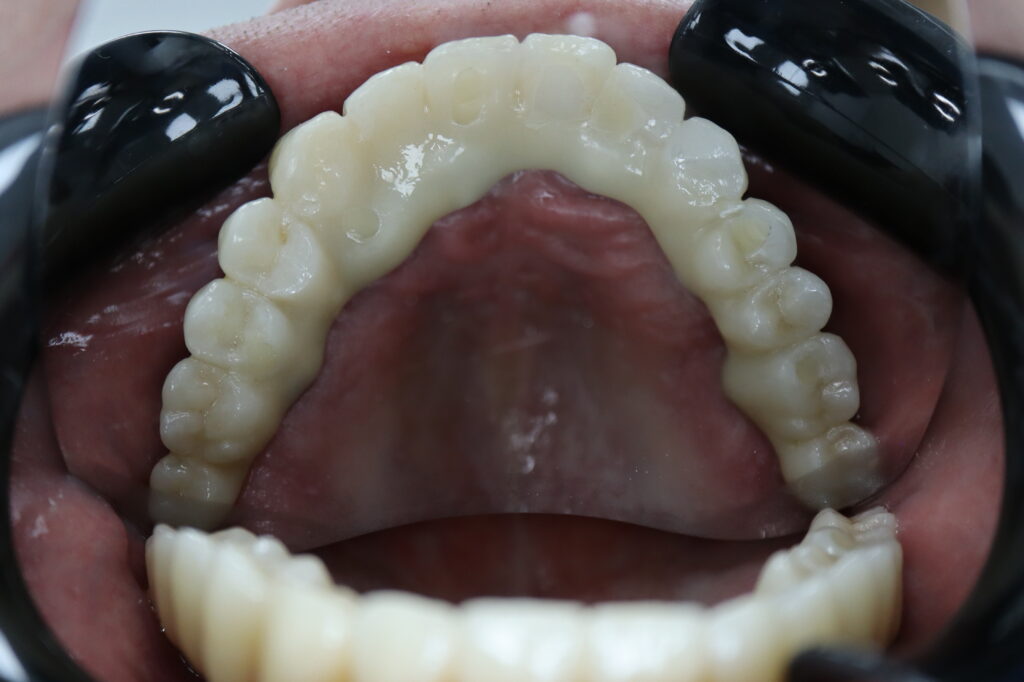

Лечение начато с выбора материала для будущей конструкции (диоксид циркония на титановой балке) и цвета.

Был установлен временный протез из PMMA, максимально воссоздающий форму и цвет (А3) будущей конструкции.

Спустя 25 дней был зафиксирован протез с опопрой на дентальные имплантаты из диоксида циркония с армированием из титана.